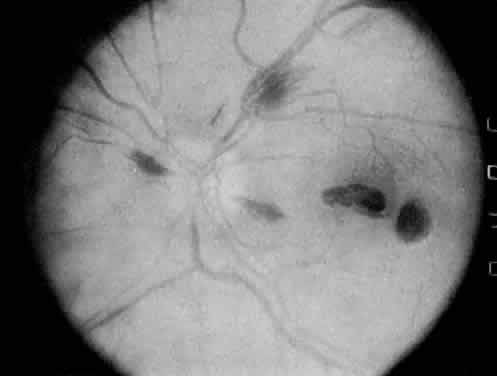

The most common ocular manifestations of TTP include papilledema, extraocular muscle palsies, and visual field defects, which usually are secondary to concomitant CNS involvement.75 Retinal findings consist of hemorrhages, retinal vascular occlusions, and serous detachments76,77 (Figs. 8 to 10). The cause of the serous detachments appears to be focal occlusion of the choriocapillaris resulting in retinal pigment epithelial damage and blood-retinal barrier disruption.76,77 Findings on fluorescein angiography are characterized by focal areas of nonperfusion of the choriocapillaris associated with late leakage into the subretinal space76 (Fig. 11). This is consistent with histopathologic studies that show occlusion of the choriocapillaris and large choroidal vessels, presumably by fibrin, with overlying necrosis of thepigment epithelium.75,76 TTP also has been linked in one case report with Purtscher retinopathy.78

Fig. 9. Fluorescein angiogram of patient with thrombotic thrombocytopenic purpura and vascular-occlusive disease. (Courtesy of William Mieler, MD.)

Fig. 11. Fluorescein angiogram of patient with thrombotic thrombocyto-penic purpura showing late choroidalhyperfluorescence caused by focal areas of choriocapillaris nonperfusion. (Courtesy of Jerry Neuwirth, MD.)